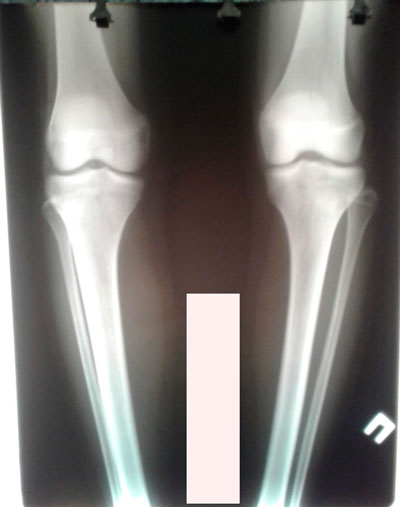

Исходник - 16 лет.

Дата операции - 22.06.2019г.

Ротация с обеих сторон.

Дата операции - 22.06.2019г.Дата снятия аппаратов - 06.09.2019г.

Срок сращения - 76 дней.